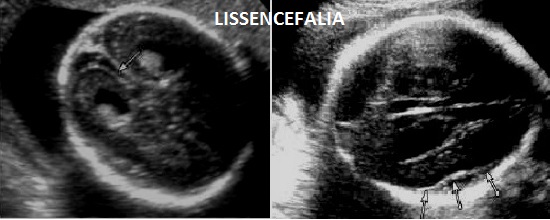

La sindrome di Miller-Dieker o lissencefalia tipo 1 è un'alterazione dello sviluppo cerebrale caratterizzata da assenza o riduzione delle circonvoluzioni cerebrali conseguente a disturbi della migrazione neuronale nella corteccia cerebrale. Dal punto di vista genetico è legata al mutazioni de novo del gene LIS1 sul cromosoma 17p13.3.

Le manifestazioni della malattia sono la lissencefalia (che può variare dalla agiria o pachigiria frontale fino alla agiria generalizzata) ed i tipici dismorfismi facciali (fronte sfuggente, naso corto, ponte nasale ampio e piatto, labbro superiore protrudente, micrognazia).

I segni ecografici che possono condurre alla diagnosi si manifestano tra la fine del II trimestre ed il III trimestre per cui la diagnosi prenatale, quando possibile, è tardiva. I segni sono: lissencefalia, microcefalia progressiva, IUGR, polidramnios, dismorfismi facciali.

La diagnosi prenatale può essere fatta nel III trimestre quando si completa la differenziazione dell'insula; il sospetto può arrivare dall' osservazione della colpocefalia o della ventricolomegalia borderline; a 30-32 settimane il persistere di circonvoluzioni lisce è indicativo di lissencefalia. La coesistenza di dismorfismi facciali e frequentemente la diminuzione dei movimenti attivi fetali e il polidramnios aiutano nella diagnosi.